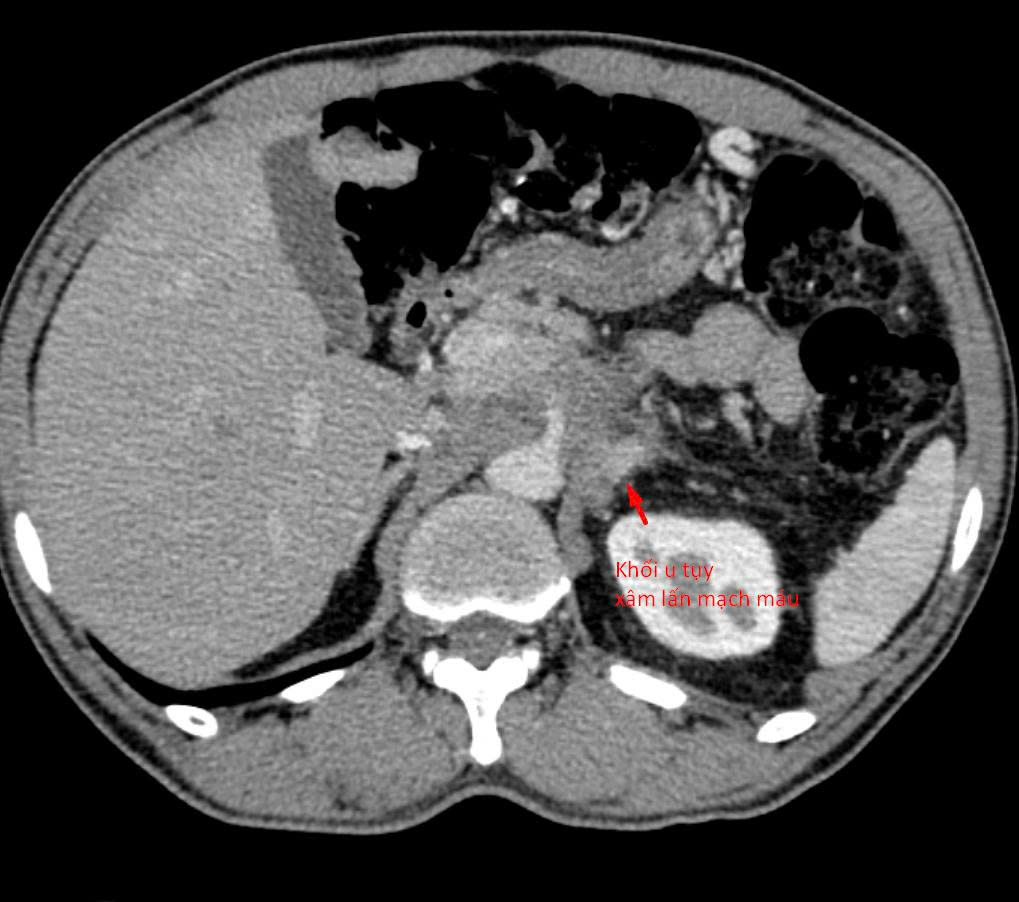

Bệnh nhân suy thận lọc máu tại Bệnh viện Thanh Nhàn (ảnh: N.M).